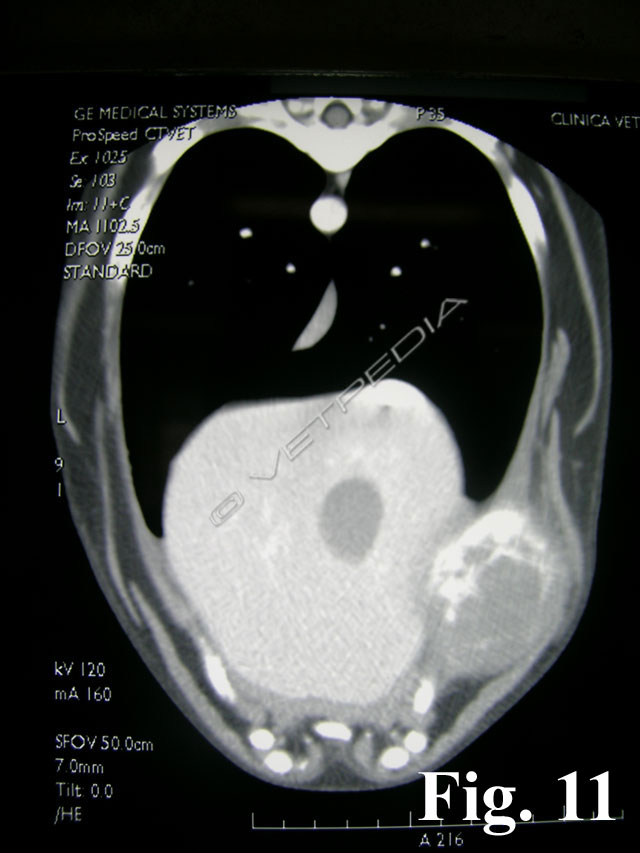

{{/_source.additionalInfo}}L'osteosarcoma è un tumore che può svilupparsi sia nel cane che nel gatto.Nel cane rappresenta l’85-98% dei tumori ossei in questa specie animale (Liptak et al., 2004b; Dernell et al., 2007). Sono più frequenti le localizzazioni appendicolari (75%) ma può anche svilupparsi a carico dello scheletro assiale (24%) e occasionalmente in sedi e